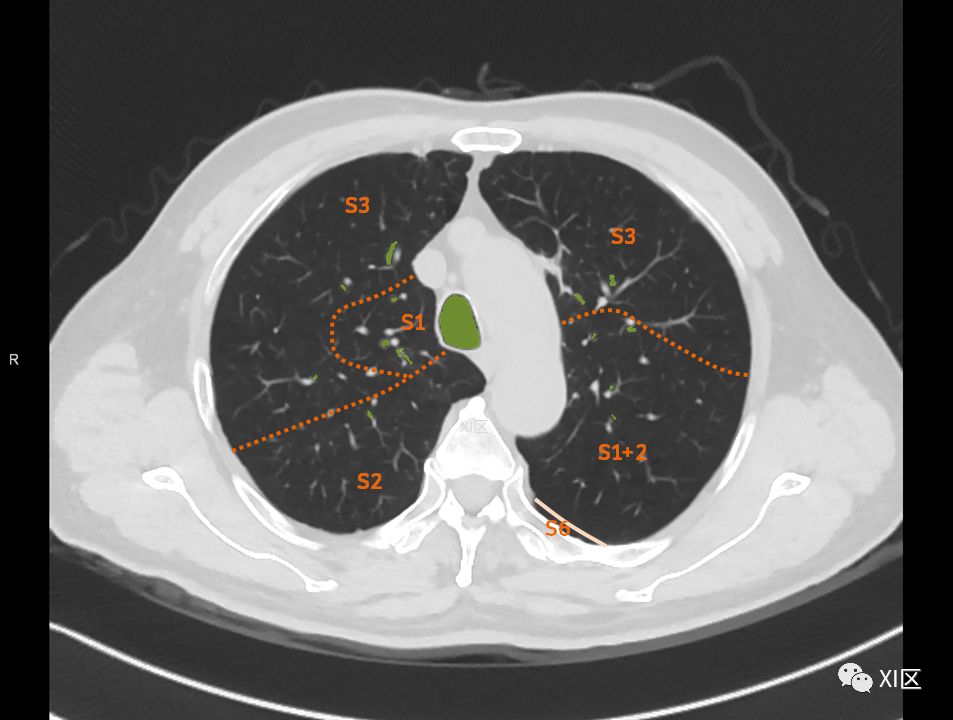

肺的分段

肺的断层分段示意图

在进行肺的分段时,可以上下观察浏览,沿着相应气管的走形可以更容易准确地进行分段。